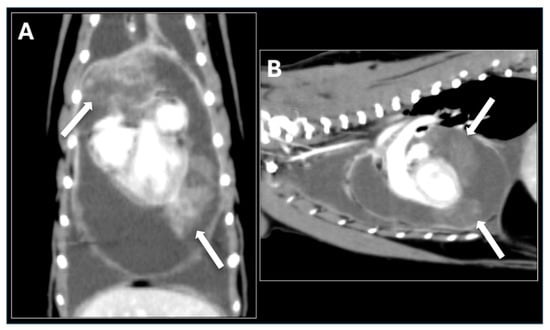

2.2. Referral and Diagnostic Evaluation

2.3. Surgical Management and Intraoperative Findings